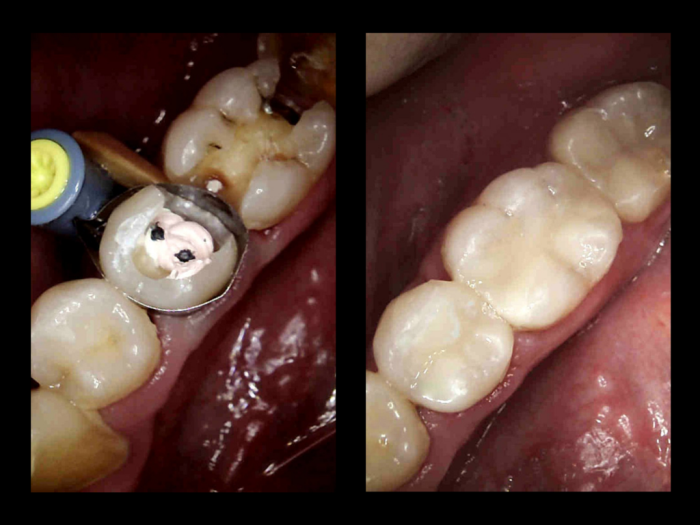

Before and After Direct Fillings